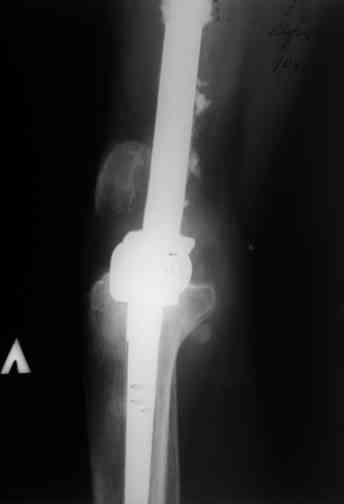

После нескольких некрэктомий, проведения аутодермопластики и заживдения ожоговой раны через 2 месяца после травмы произведен открытый остеосинтез левой бедренной кости штифтом и пластиной (деротационной) [image 01, 02]. Через 1 год и 7 месяцев после травмы у больного диагностированы ложный сустав и хронический остеомиелит левой бедренной кости. Произведено удаление металлических фиксаторов, секвестрэктомия и остеосинтез бедренной костивнешним двухплоскостным стержневым аппаратом [image 03, 04] .